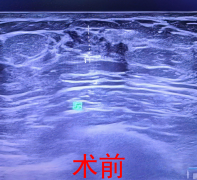

近日,我院骨科团队成功为一位91岁高龄的股骨粗隆间骨折患者实施了切开复位内固定术。术后恢复良好,患者已于1月10日在协助下下床行走,展现了在高龄患者中实施积极手术干预与

近期,新余北湖医院通过多学科协作,为一名89岁高龄的股骨颈骨折患者成功实施人工关节置换术。患者术后恢复顺利,如期实现下床行走,展现了医院在高龄骨科疾病救治方面的综合